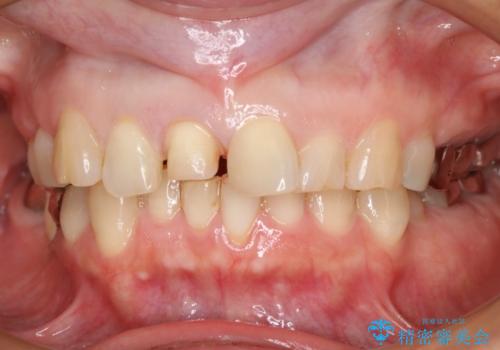

前歯が欠けたので治してほしい

- 上顎前歯の歯冠部が破折した患者様です。神経にまでは到達していなかったので精密根管治療は行わず、審美性を考慮し、オールセラミッククラウンでの治療を選択しました。